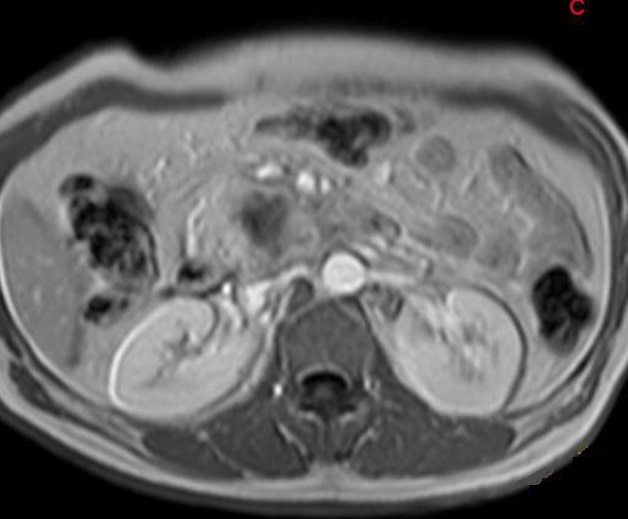

Aspect lesionaire d'une

adenocarcinoma cephalique du pancreas . Le tumeur

est en globulaitre , a bord peu nette et legerement a

hypointense plus que le parenchyme saint du pancreas .

Image radiologique IRM ponderee T1 Fat Sat en coupe

axial |

Une autre cas de

adenocarcinoma du pancreas ponderee sur T2 . Image

radiologique du tumeur est hyposignal avec

image de contenue heterogene hypersignal (

fleche rouge ) |